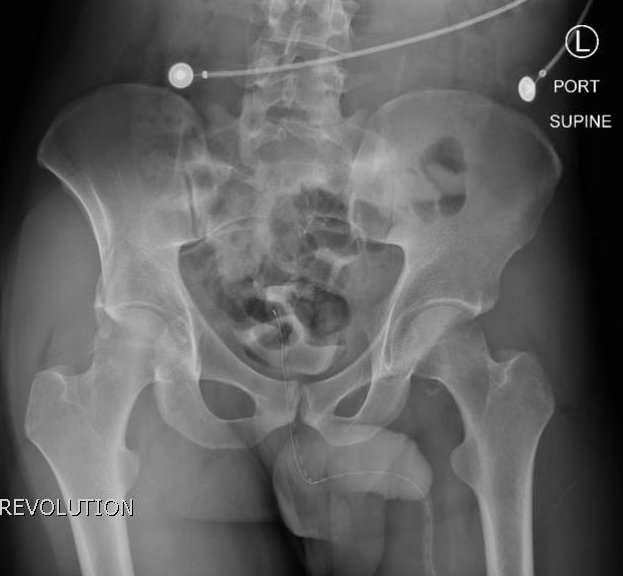

The initial radiograph of the pelvis revealed bilateral hip dislocations. Small bony fragments were noted in the right hip joint, suggestive of an underlying fracture. The sacroiliac joints and the pelvic ring were intact. In the emergency department, bilateral hip reductions were performed using the Captain Morgan technique.1 The post-reduction film showed reduction of the bilateral hip dislocations with extensive comminuted and displaced fractures of the right and left acetabula.